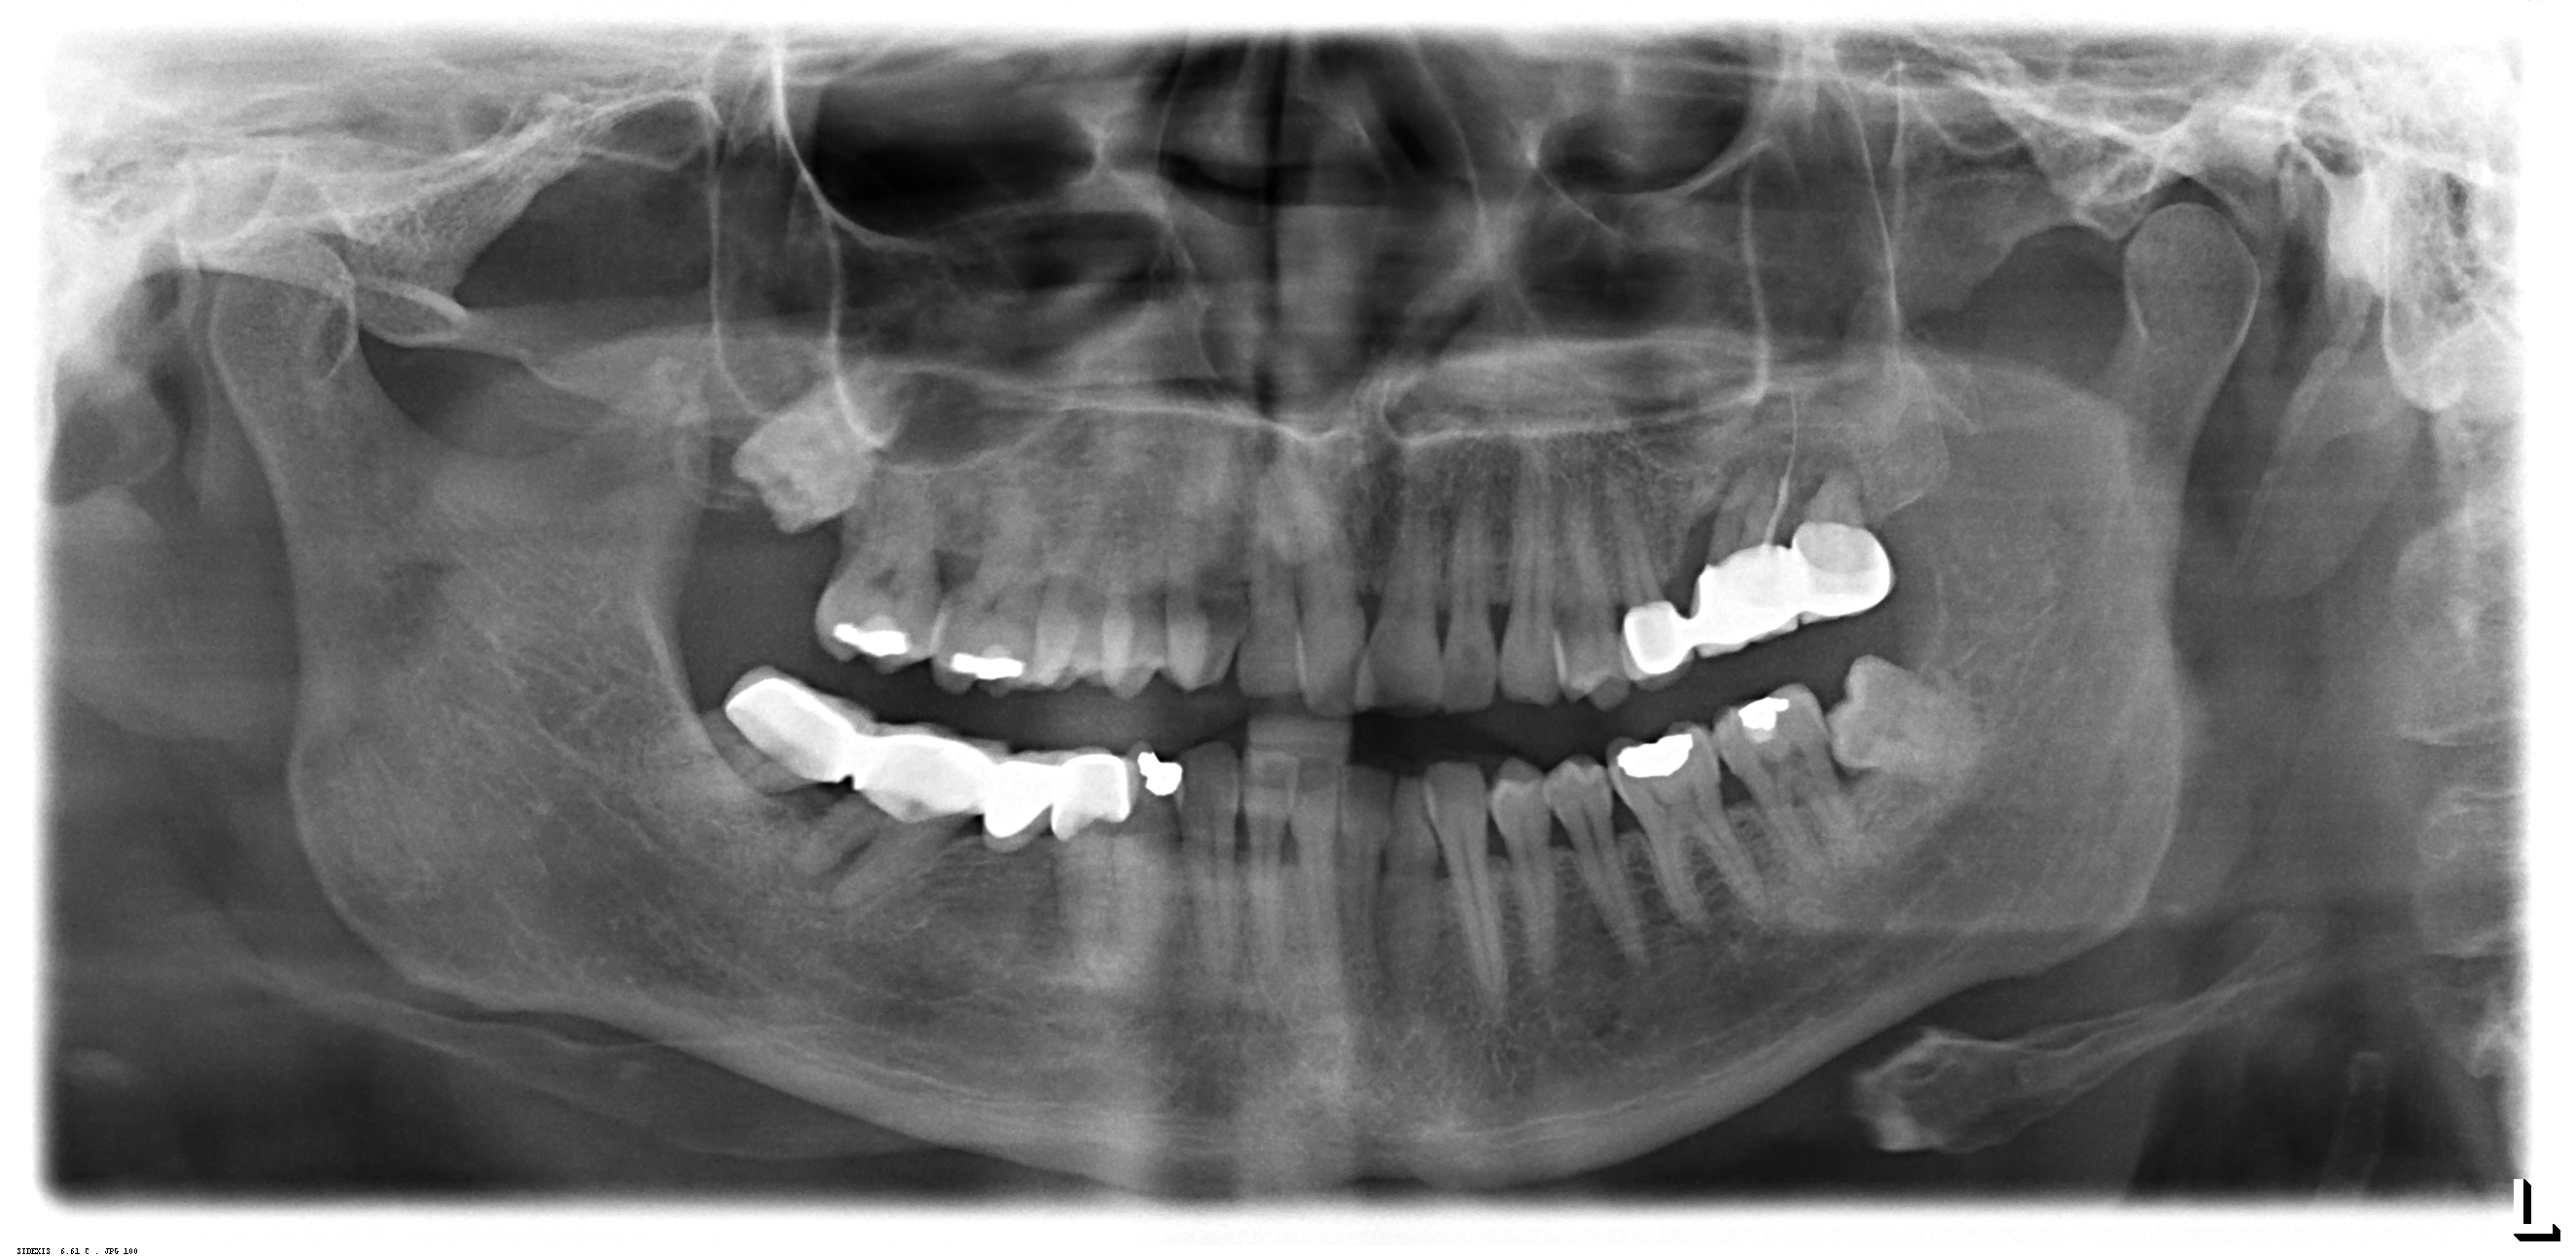

1/19 - Initial situation after root channel treatmentSinus lift two-stage with cerabone® and Jason® membrane - Prof. Dr. Dr. D. Rothamel

2/19 - Detail of OPGSinus lift two-stage with cerabone® and Jason® membrane - Prof. Dr. Dr. D. Rothamel

3/19 - OPG after tooth extraction and healing showing vertical and lateral defect after cystectomy and tooth extractionSinus lift two-stage with cerabone® and Jason® membrane - Prof. Dr. Dr. D. Rothamel

4/19 - Detail of OPGSinus lift two-stage with cerabone® and Jason® membrane - Prof. Dr. Dr. D. Rothamel